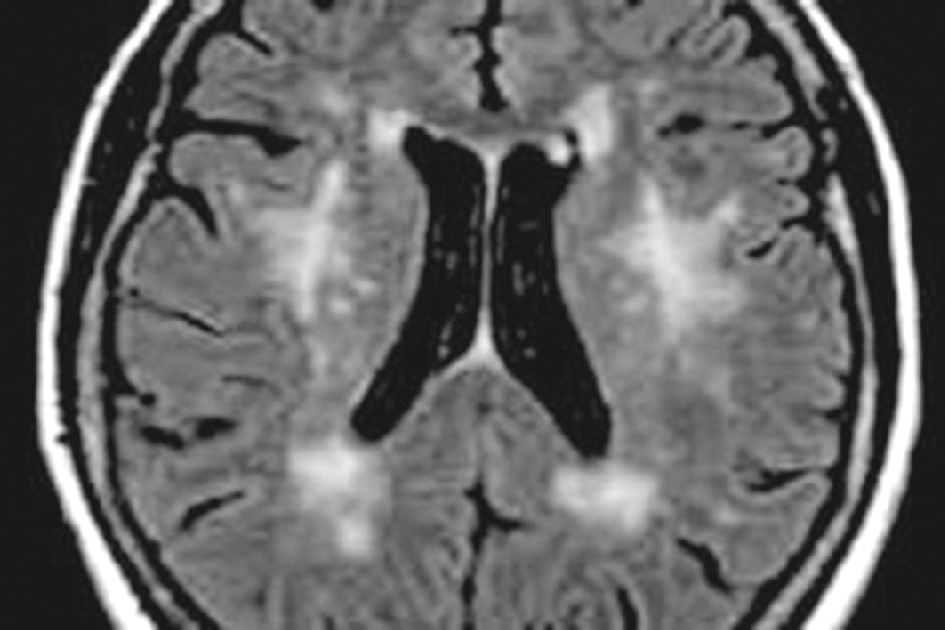

• L’IRM cérébrale montre des images caractéristiques (fig. 19.2).

Fig. 19.2

État lacunaire : IRM cérébrale.

L’IRM cérébrale montre les images caractéristiques sous forme de multiples hypersignaux au sein des noyaux gris centraux.Cette coupe axiale en séquence FLAIR met en évidence de multiples hypersignaux punctiformes bilatéraux au niveau de la substance blanche profonde, en particulier autour des ventricules latéraux et dans les régions fronto-pariétales. Ces lésions correspondent à des séquelles ischémiques de petite taille, appelées lacunes, typiques d’un état lacunaire. L’aspect est symétrique, sans effet de masse ni œdème périlésionnel. Les ventricules sont modérément élargis, ce qui peut traduire une atrophie cérébrale chronique. Ce tableau est caractéristique d’une microangiopathie cérébrale liée à des facteurs vasculaires comme l’hypertension artérielle.